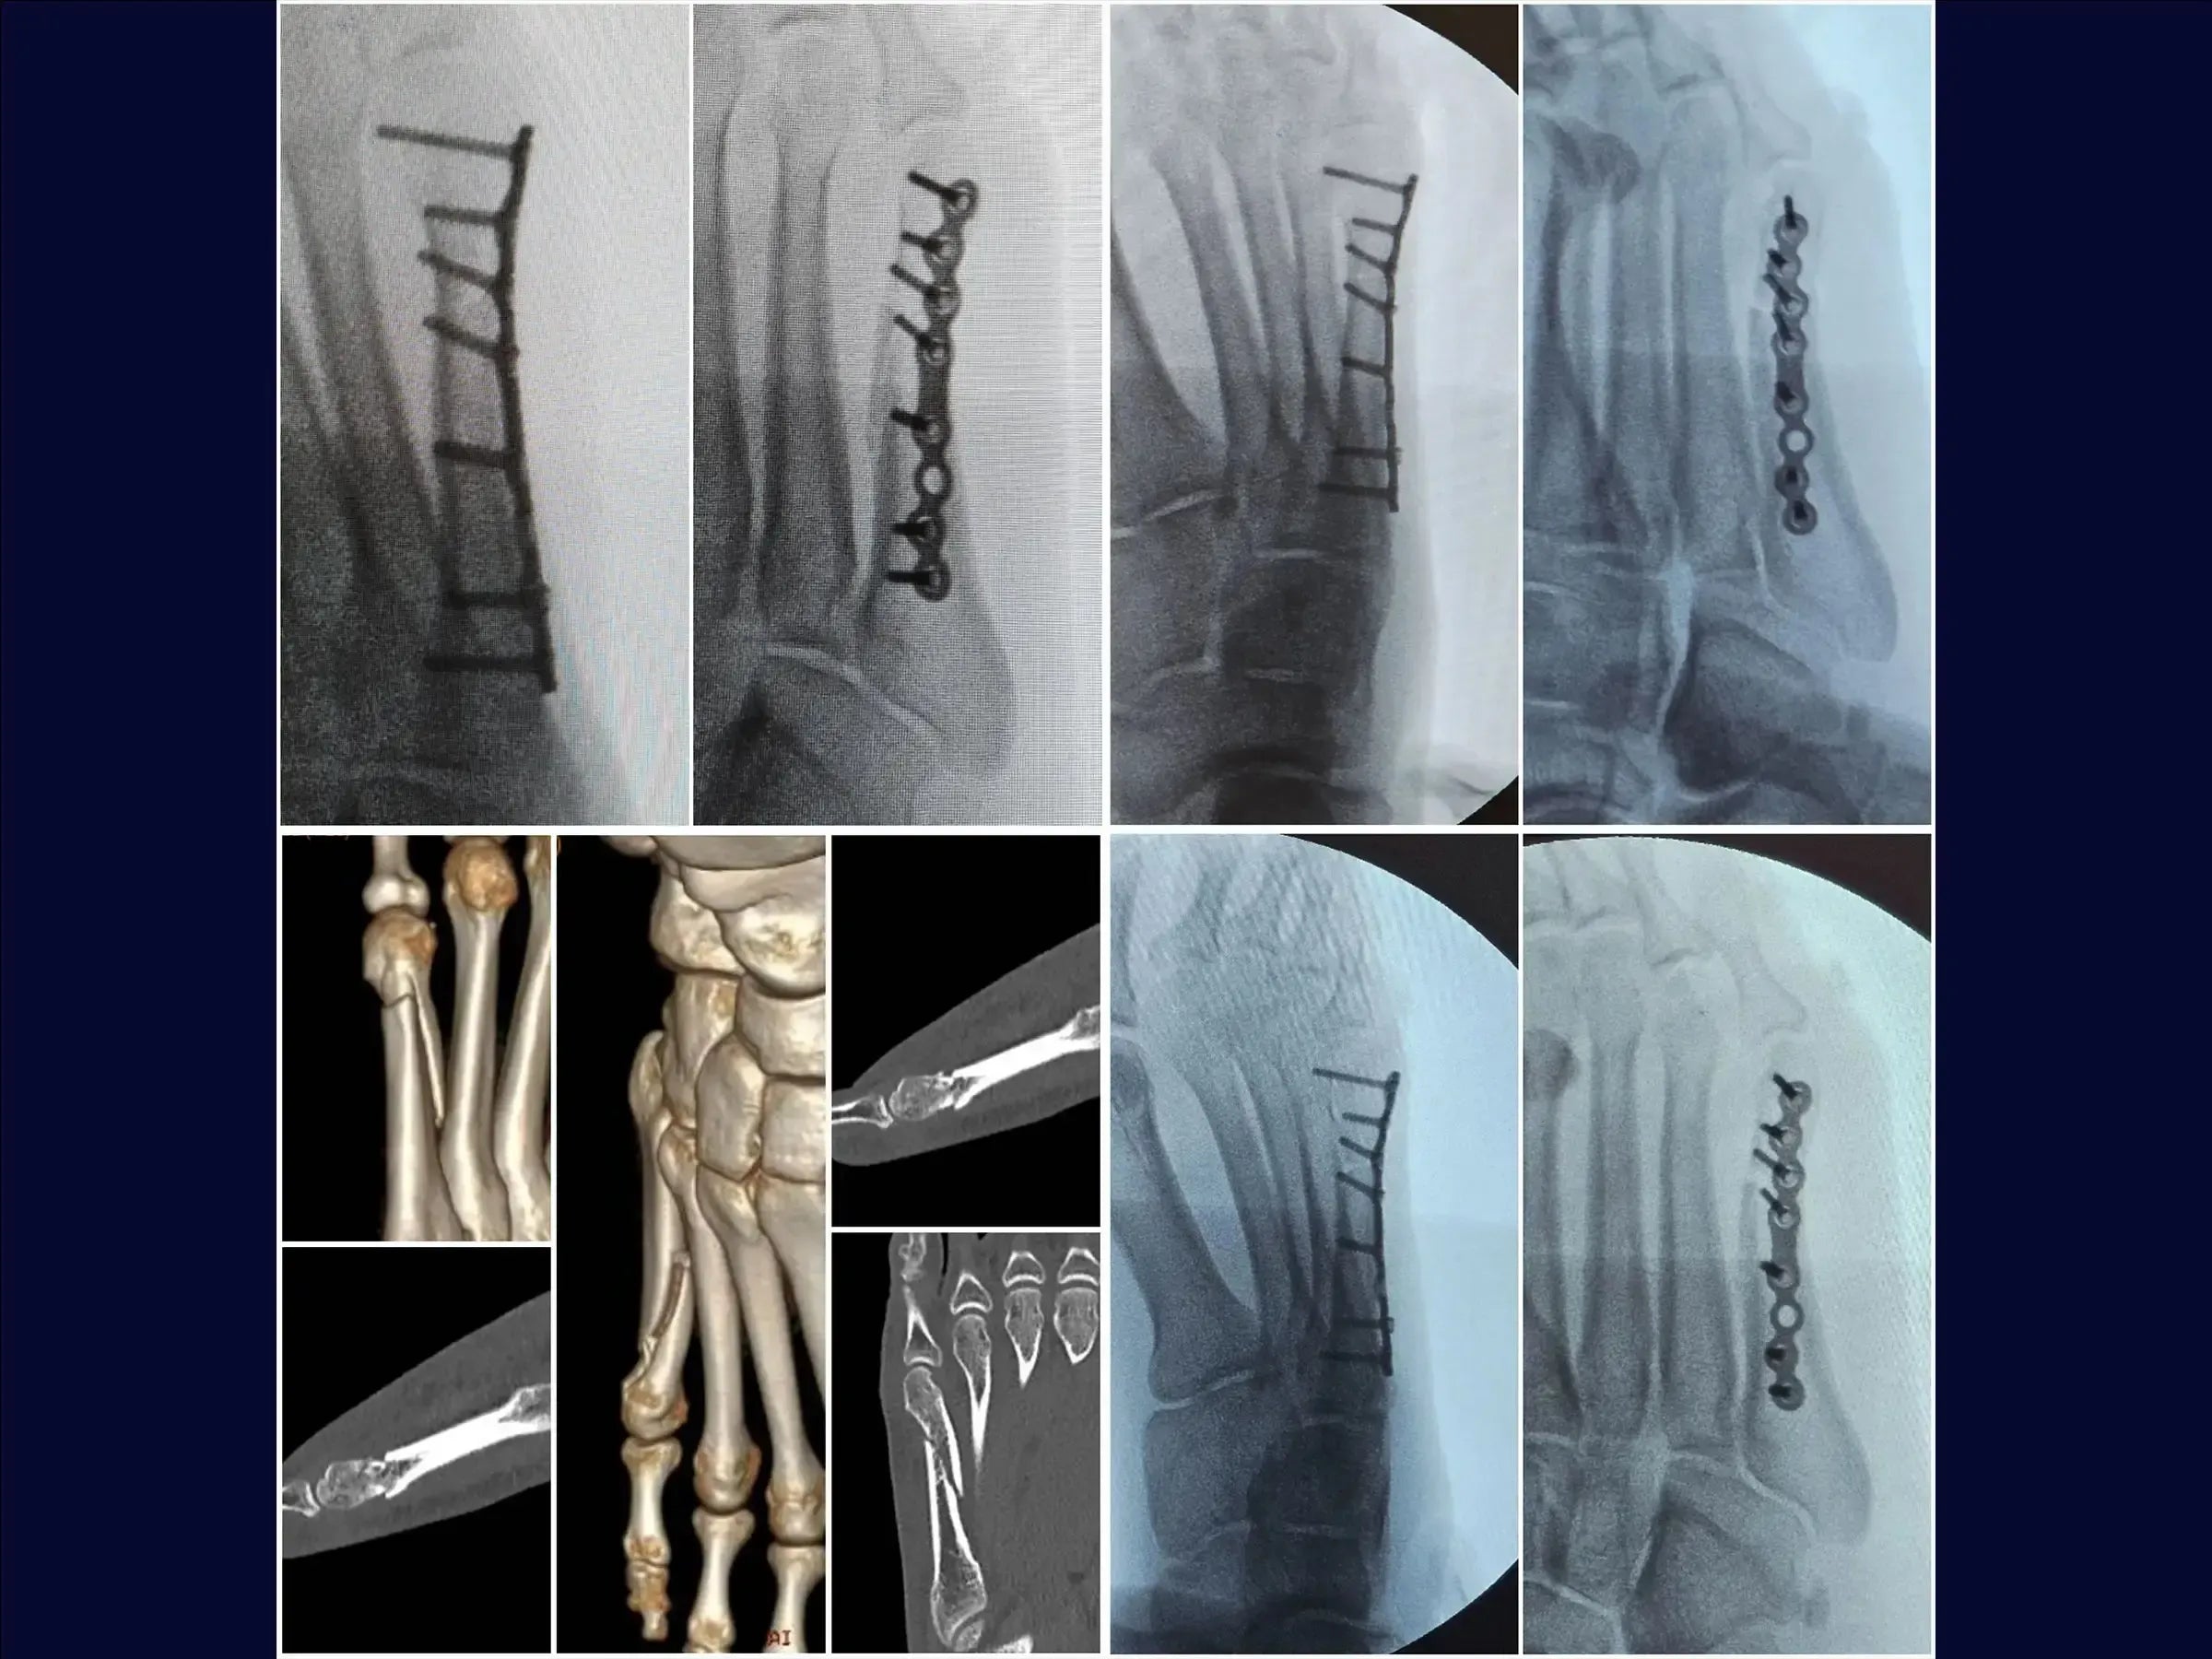

Mejore sus habilidades en el tratamiento quirúrgico de fracturas desplazadas del quinto metatarsiano. Este procedimiento requiere una reducción anatómica cuidadosa para evitar la metatarsalgia o la disfunción de la marcha, especialmente en pacientes jóvenes y atletas. Esta capacitación detalla el procedimiento quirúrgico con placa de bloqueo y tornillos, con énfasis en la rápida recuperación funcional y el retorno a la actividad deportiva.

- Tratamiento quirúrgico de las fracturas desplazadas del quinto metatarsiano.

- Reducción anatómica y fijación estable con placa de bloqueo.

- Evaluación y planificación del acceso: análisis de radiografías para identificar la angulación de la fractura y la posibilidad de alteración de la carga de peso, metatarsalgia o disfunción de la marcha.

- Reducción de la fractura y estabilización provisional: Identificación de los vértices de la fractura, reducción bajo visualización directa con pinza de reducción y estabilización provisional con agujas de Kirschner, evitando la zona de la futura placa.

- Fijación Definitiva con Placa Bloqueada: Colocación de una placa minifragmentaria de perfil bajo, utilización de tornillos largos para una adecuada distribución de la carga y reducción de la necesidad de futuras extracciones.

- Cierre y resultados: Cierre plano, con demarcaciones para resultados estéticos. La fijación estable permite la carga temprana con calzado de suela rígida.